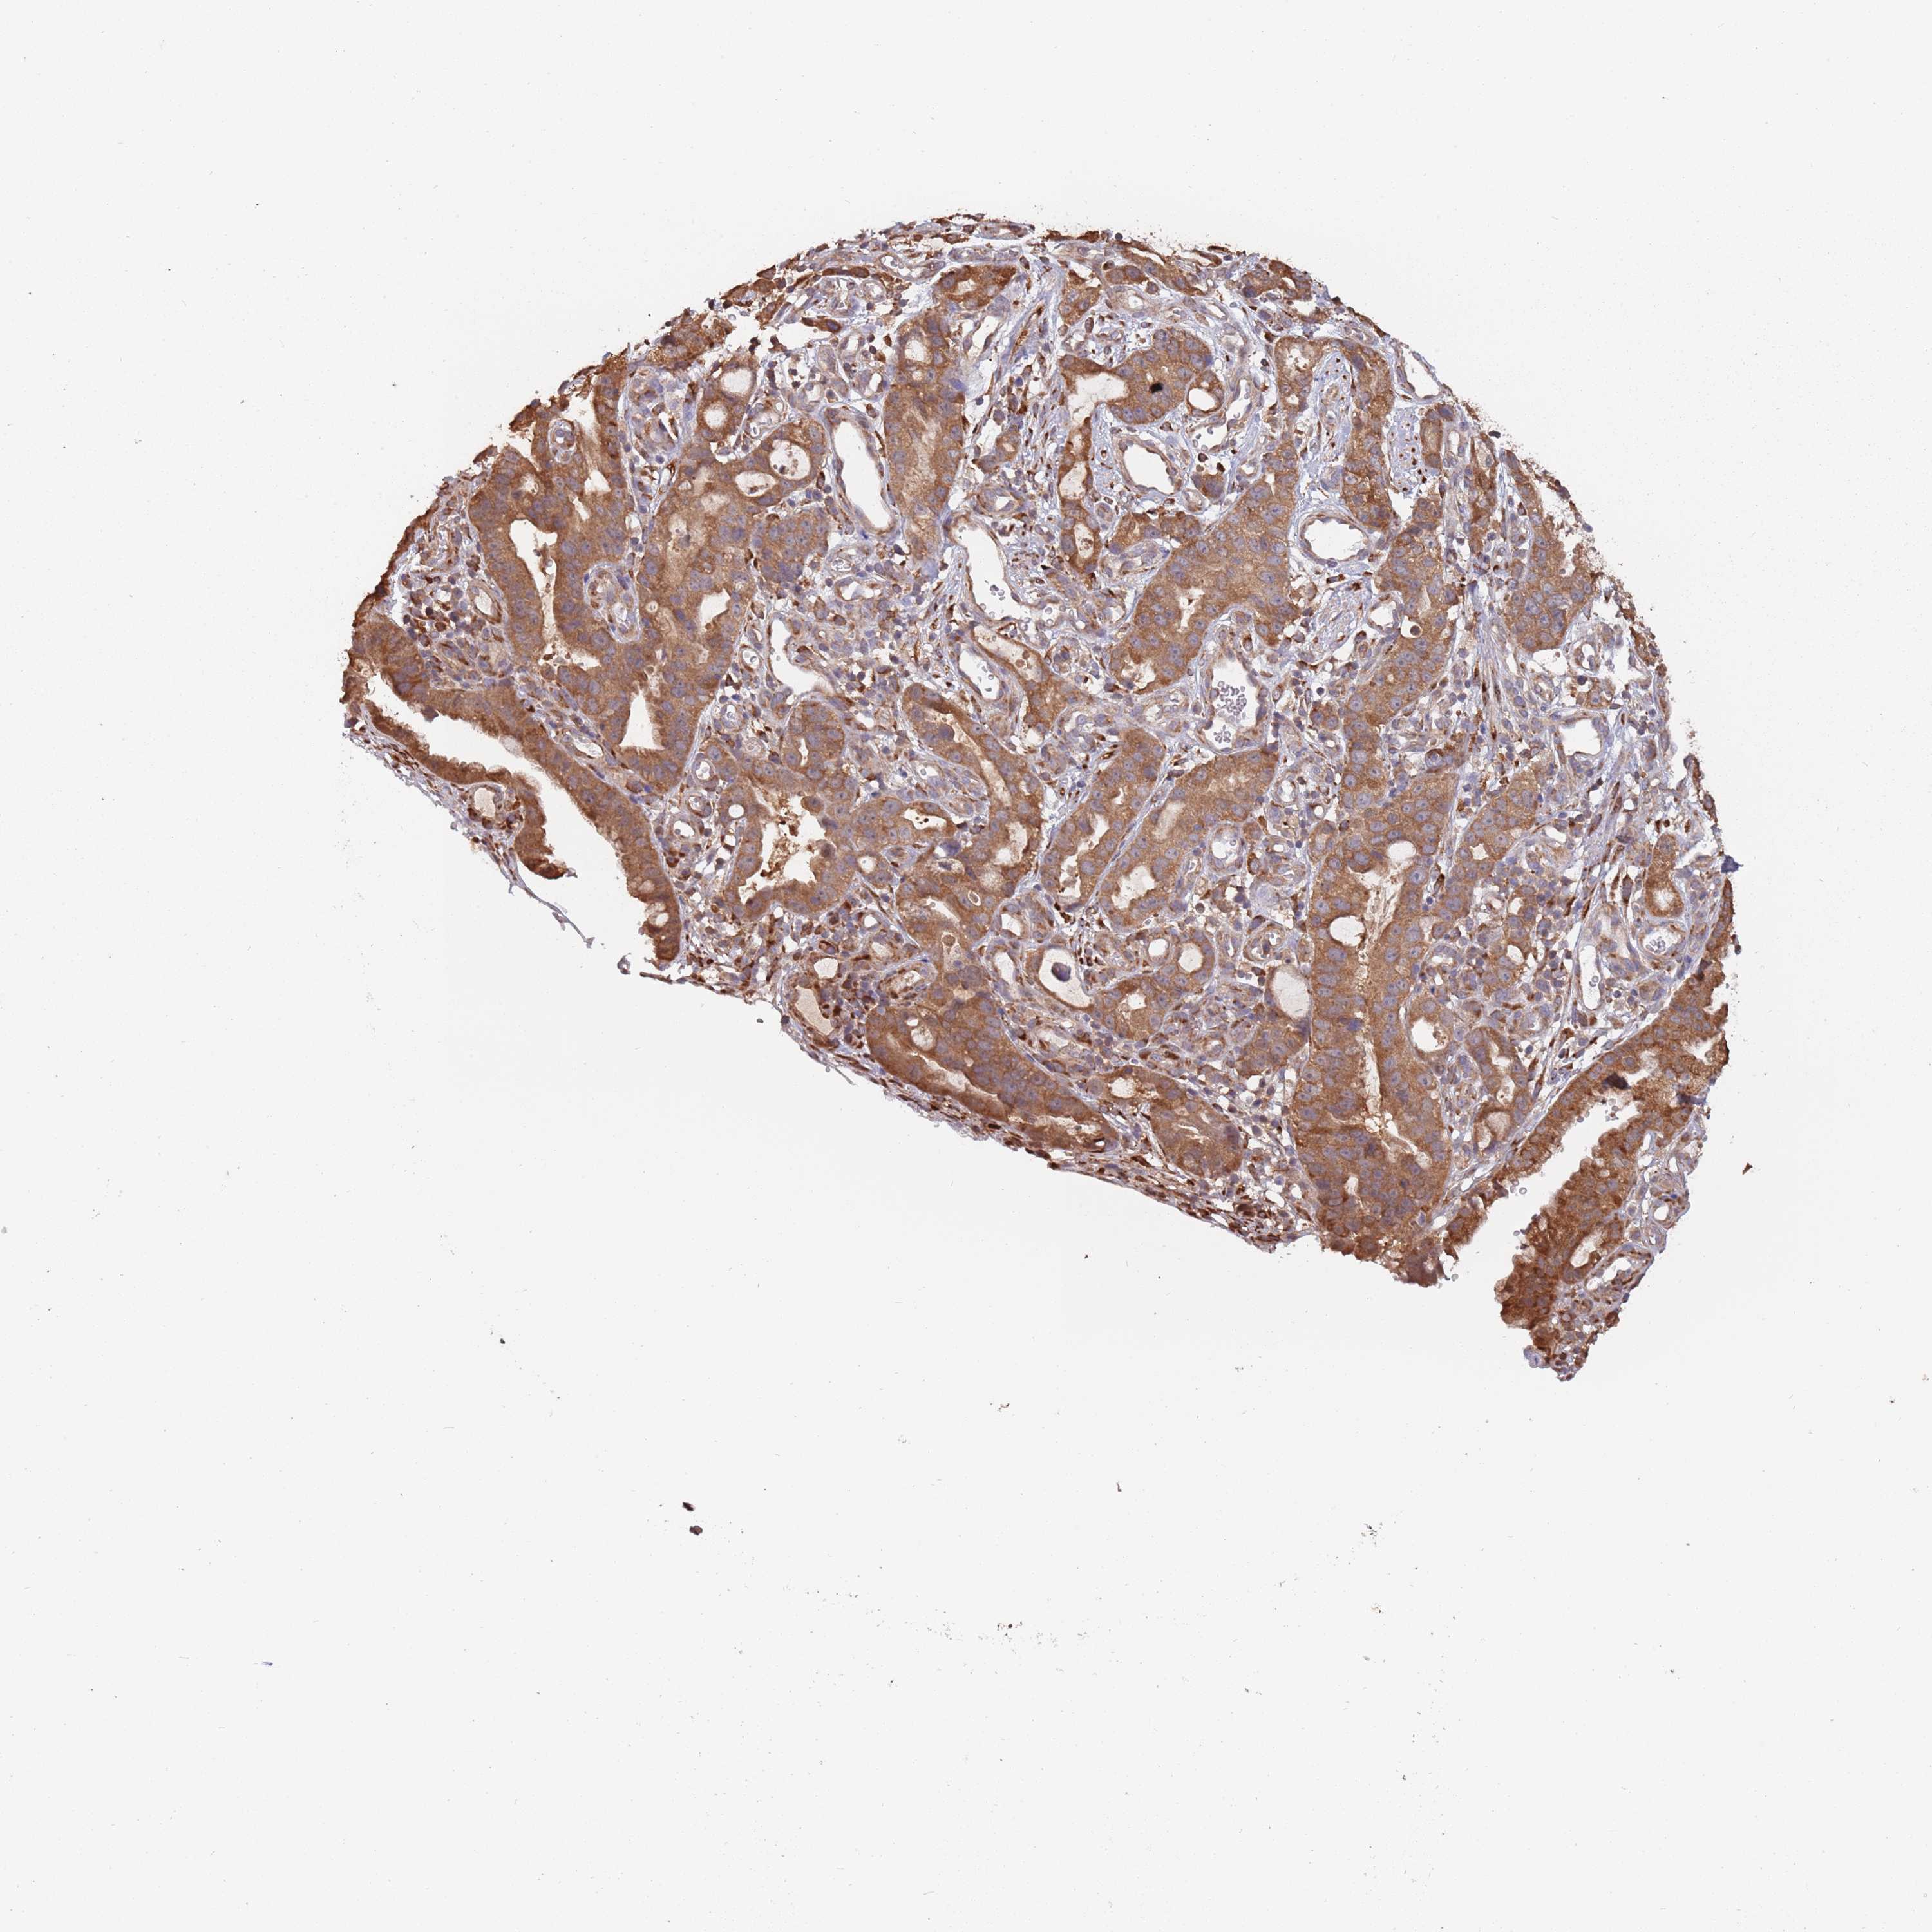

STOMACH CANCER - Protein expressioni

A mouse-over function shows sample information and annotation data. Click on an image to view it in a full screen mode. Samples can be filtered based on level of antibody staining by selecting one or several of the following categories: high, medium, low and not detected. The assay and annotation is described here.

Note that samples used for immunohistochemistry by the Human Protein Atlas do not correspond to samples in the TCGA dataset.

Antibody stainingi

Antibody staining in the annotated cell types in the current human tissue is reported as not detected, low, medium, or high, based on conventional immunohistochemistry profiling in selected tissues. This score is based on the combination of the staining intensity and fraction of stained cells.

Each image is clickable and will lead to virtual microscopy that enables deeper exploration of all samples and also displays staining intensity scores, fraction scores and subcellular localization as well as patient and tissue information for each sample.

Antibody HPA040924

Antibody HPA042539

Staining

High

Medium

Low

Not detected

Intensity

Strong

Moderate

Weak

Negative

Quantity

>75%

75%-25%

<25%

None

Location

Nuclear

Cytoplasmic/membranous

Cytoplasmic/membranous,nuclear

Adenocarcinoma, NOS

Adenocarcinoma, High grade